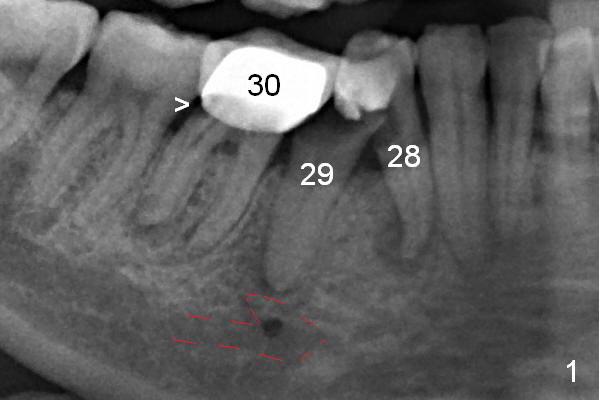

The patient returns for implant placement 11 months post extraction of #28 and 29. With flapless manner, initial osteotomy happens to drop into the original socket of #28 (Fig.4). After use of 3.3 mm Magic Drill (MD) and Final Drill for 15 mm, a 4x11 mm dummy implant is placed (Fig.5). It appears that the implant is long for the site (red dashed line: Mental Loop). However, a definitive implant (4x9 mm, IBS) has difficulty to reach its depth (Fig.6). After several rounds of untorque and retorque, the implant does not seat completely (Fig.7, implant driver disengagement) with autogenous bone placed distal (>). Retrospectively, a larger MD should have been used (3.8 mm) for complete seating in the dense bone. In fact she is post breast cancer treatment with 50% chance of relapse. The patient returns for follow up 1.5 months postop (Fig.8). The wound has healed. Impression is taken 5 months postop (Fig.9). When the crown is cemented, food impaction is an issue between the implant crown and crown at #30. Since the tooth #30 is mesially tilted with distal open margin and apical infection, the tooth will be extracted. Osteotomy is going to be initiated in the mesial slope of the mesial socket (Fig.9 red line). An implant will be placed more or less in the mesial socket (green box).